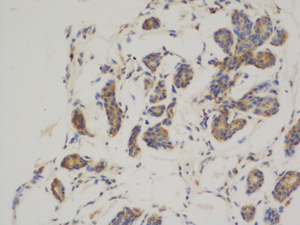

- Immunohistochemistry analysis of paraffin-embedded Human breast cancer using Bcl2 antibody.High-pressure and temperature Sodium Citrate pH 6.0 was used for antigen retrieval.